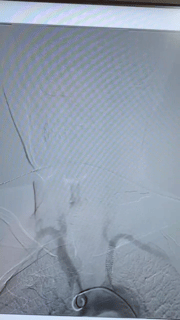

△造影显示:左侧锁骨下动脉近端闭塞

术中,李华军教授带领团队,先使用特殊导丝成功穿过左锁骨下动脉栓塞处,建立通道,然后引导球囊送至闭塞处扩张,将通道扩大,随后复查造影显示闭塞处通路打开,椎动脉盗血现象消失。撤出球囊,植入支架。完成后复查造影,显示支架释放良好,闭塞处完全开通,无残余狭窄,前向血流通畅,左椎动脉盗血消失,双上肢血压恢复一致,手术顺利完成。

△支架植入后左侧椎动脉盗血消失,血流恢复正常